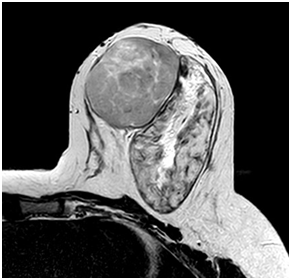

A 47year-old woman with history of a long standing palpable mass on the left breast, which was biopsied on 2006 resulting in hamartoma. She had first degree familiar history of breast cancer with her mother diagnosed younger than 50 \years of age and who later on died of that cause. The patient presented to our office, in June 2016 for progressive growth of her breast tumour. At examination her breasts were fibrous, with a palpable firm and mobile breast mass, not fixed to skin, of 8x6x5cm on the left LIQ, and another large, soft and well defined mass in left LOQ and UOQ of 10x10x5cm, There were no palpable masses in the axilla. On mammography there was a radiolucid well defined breast mass in the left LOQ and UOQ, which was stable in size and shape regarding prior mammogram of twoyears. A new dense, oval and partially defined breast mass was evident in the LIQ (Figure 1). The latter on breast ultrasound corresponded with a hypoechoic and heterogenous nodule with partially defined margins, which measured approximately 7cm. The first lesion was heterogenous and hyperechoic, measured more than 8cm, and was the previously biopsied nodule (Figure 2). She later on underwent a breast MRI that showed a round mass in the LIQ, which was hyperintense in T2, hypointense in T1, had a homogenous enhancement with a plateau curve. In the LOQ there was a well-defined mass, which was heterogenous with fibrous and fatty tissue, and did not enhance with gadolinium (Figure 3). A core biopsy of the two masses was then performed, demonstrating a biphasic fibro-epithelial lesion compatible with a PT at the LIQ, and fibrocystic changes and intraductal hyperplasia without atypia at the LOQ. On August 2016, the patient underwent a partial mastectomy, without incidents, and was sent home on the subsequent day (Figure 4). The definitive biopsy demonstrated that the tumour at the LIQ corresponded to a malignant PT (Figures 5) (Figure 6), and that the LOQ mass was a large breast hamartoma (Figures 7 & Figure 8). Posteriorly, she received 25 radiotherapy fractions, without major adverse effects. She was recently controlled with breast ultrasound and MRI that showed no residual breast lesions.

Figure 3 Preoperative breast MRI (T2 weighted image, T1 weighted image, STIR and gadolinium enhanced high resolution T1WI with fat saturation).